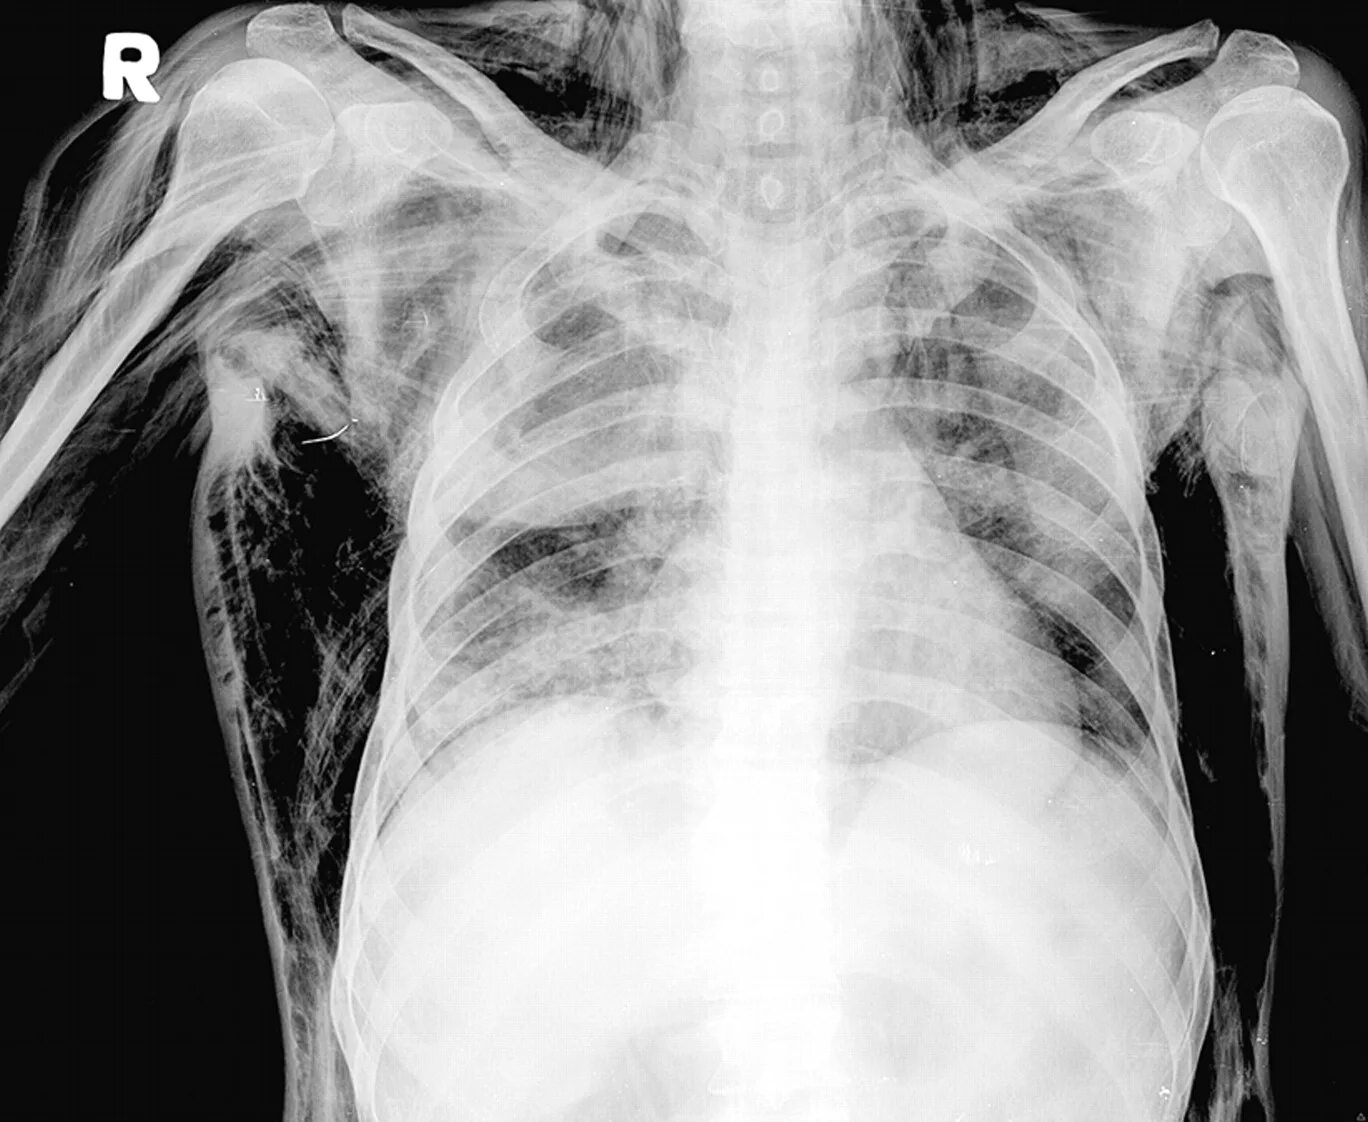

Эмфизема мягких